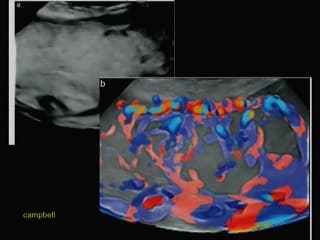

L'auteur rapporte une observation de calcifications artérielles après l'usage de laser par foetoscopie dans le cadre d'une grossesse gémellaire mono-bi pour un STT. La présence de calcifications des gros vaisseaux : aorte et AP est constatée. S'ensuit une discussion sur la physiopathologie de ces calcifications : soit des microlésions de vaisseaux par surcharge circulatoire chez le receveur ou des calcifications généralisées (GACI).